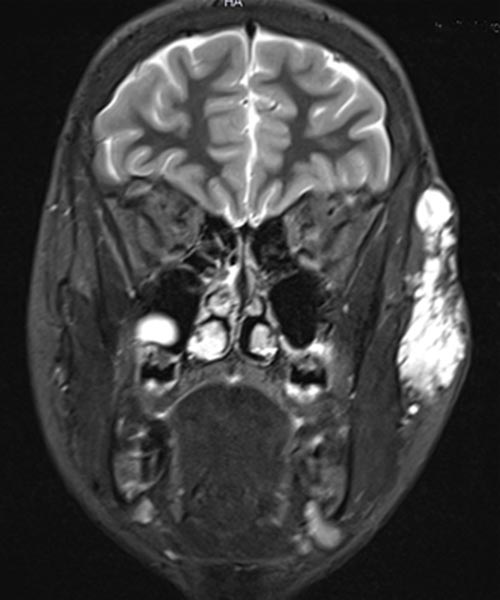

Coronal, T2-weighted fat-suppressed MRI of the face. The venous malformation typically appears very hyperintense (white).